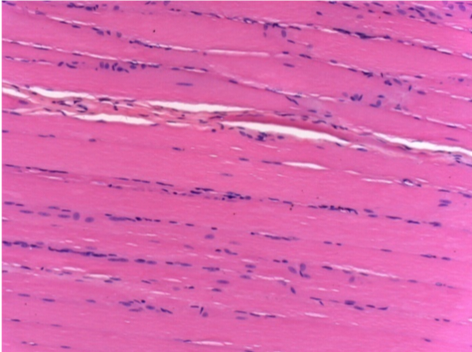

1 mes después de la inyección de Endopeel 0,1 ml en el músculo pretibial derecho.

¡Lo que se ve en negro en las imágenes no es una necrosis como podrían imaginar algunos científicos!

De hecho, hay que tener en cuenta 4 conclusiones

08